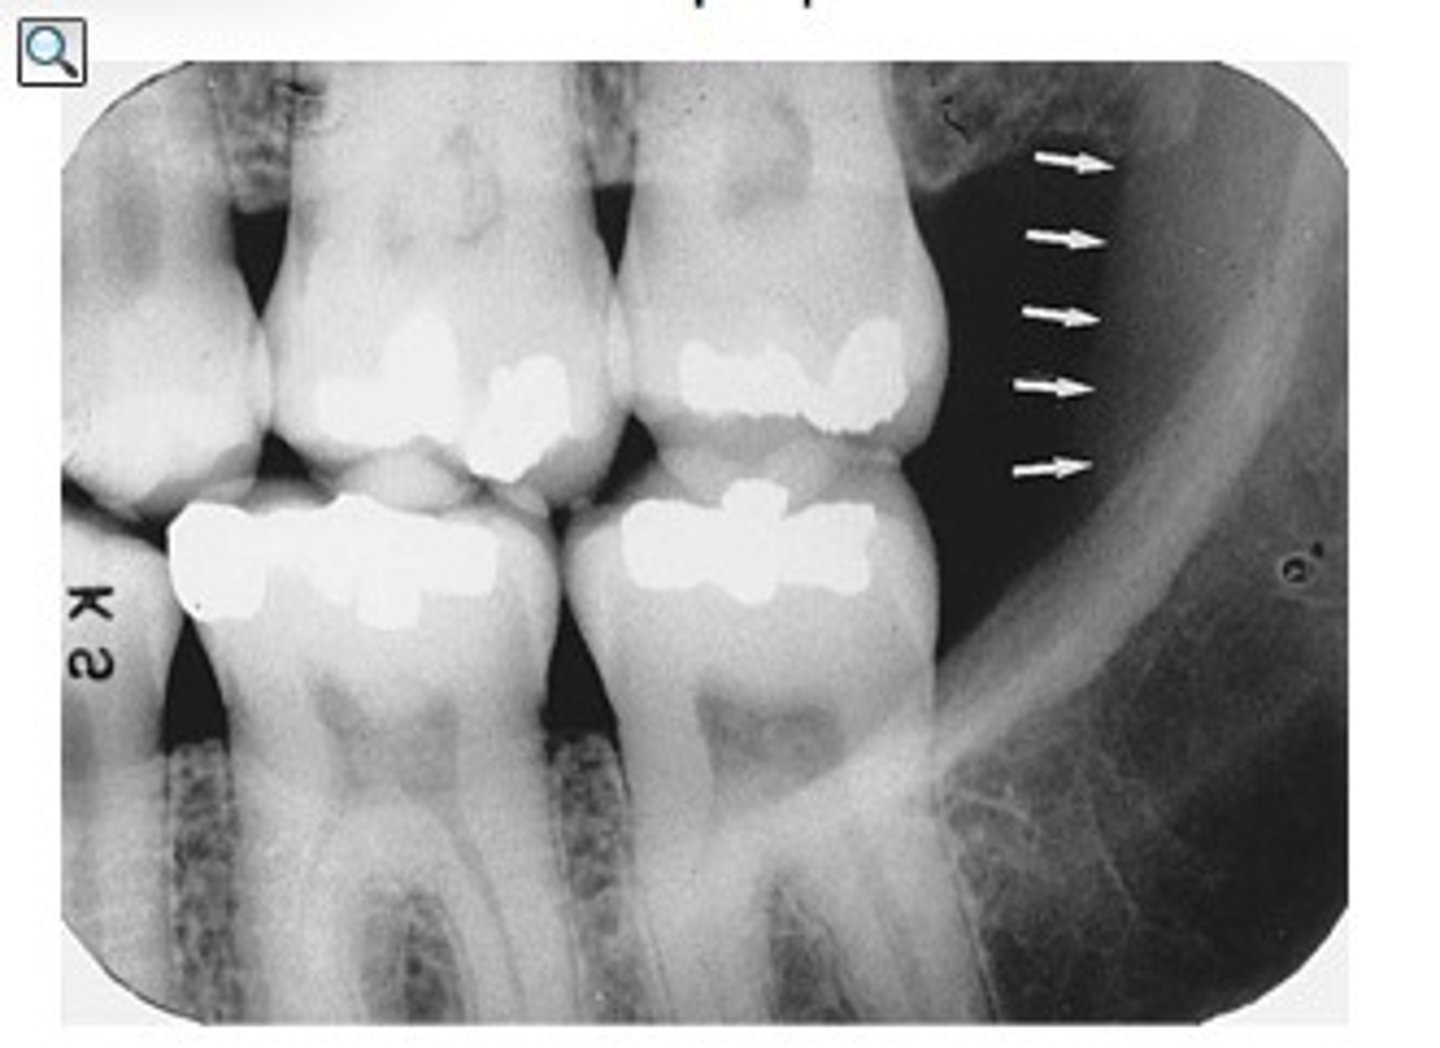

Septa within the maxillary sinus

What is the radiopaque structure seen here?